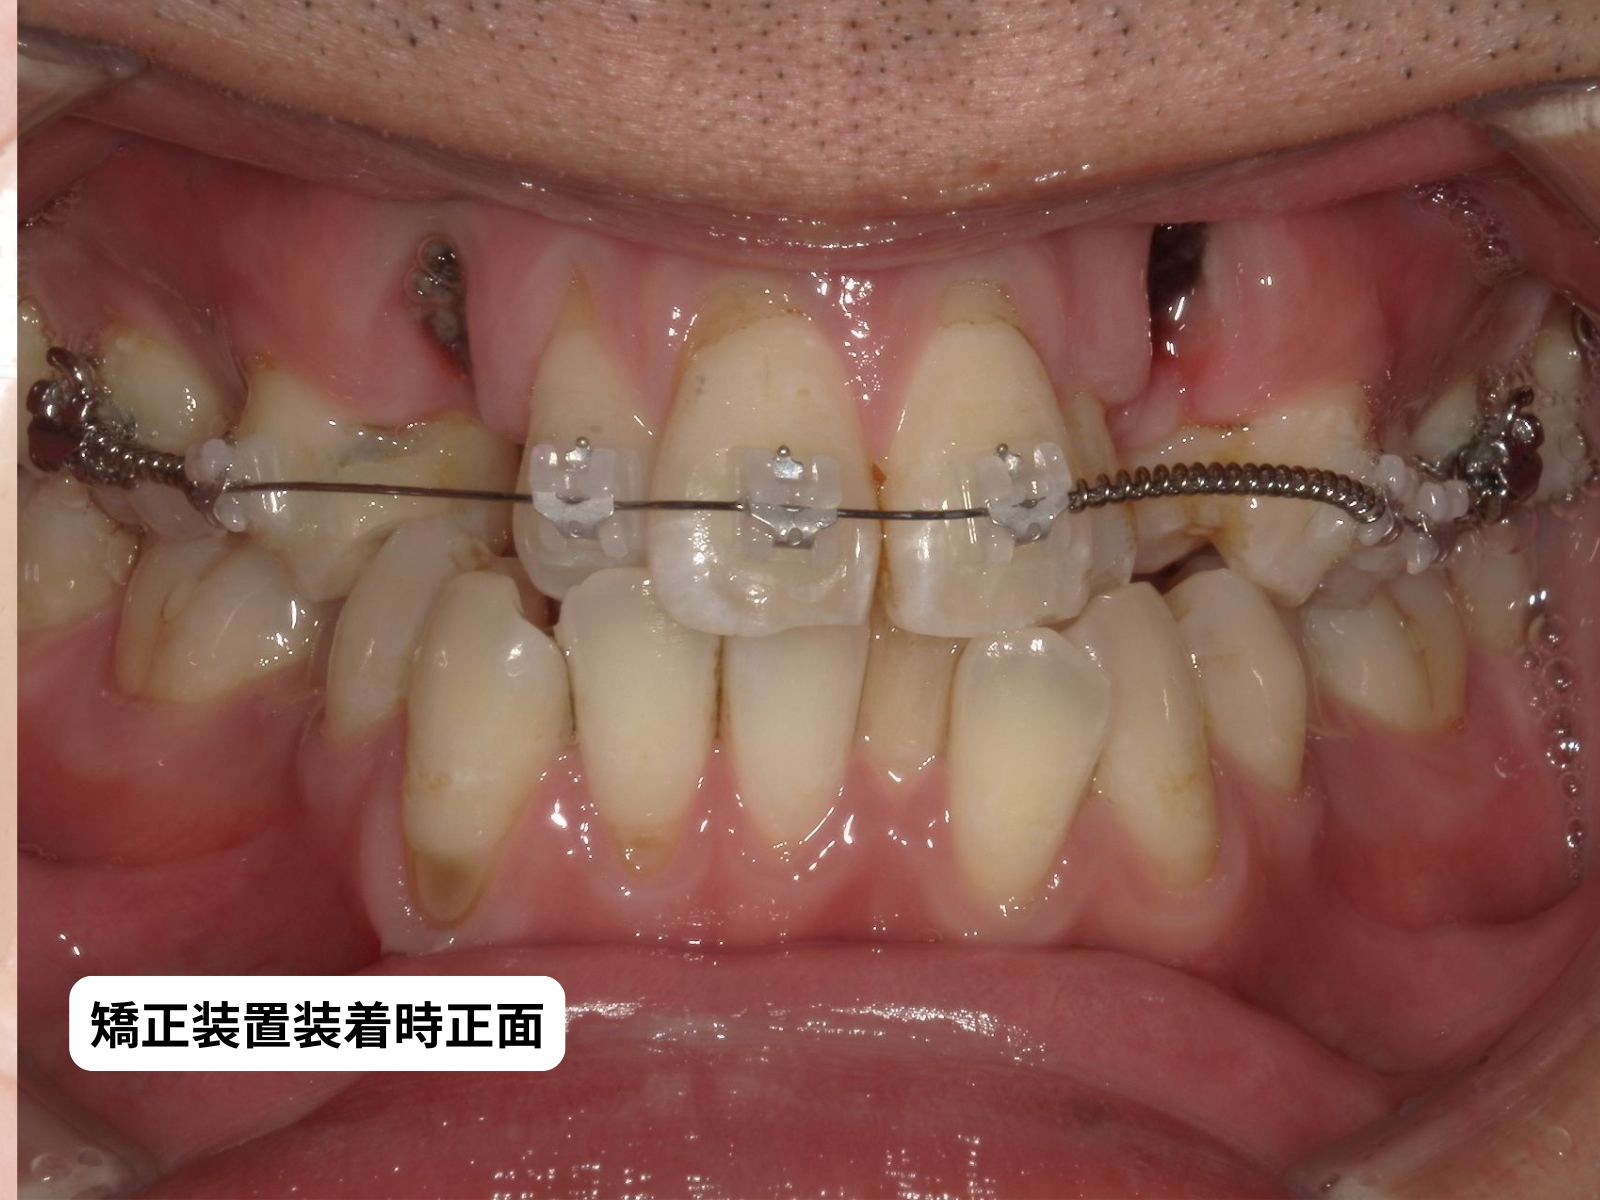

#26-写真3 装置装着 正面

矯正装置装着

歯茎が回復したことを確認してから矯正を開始